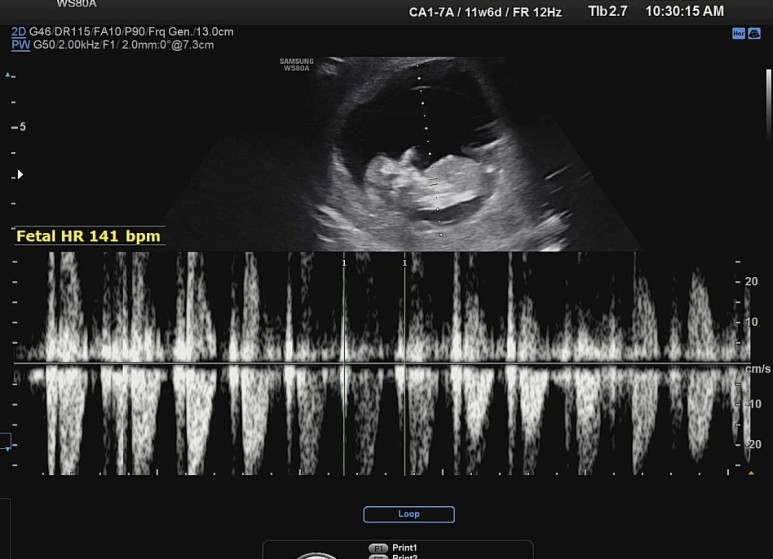

기본적으로 심장이 잘 뛰고 있는지도 보고ㅡ,

꿀잠이 오늘의 바이탈은 141bpm !

(태아 12주 평균 심장 박동수는 120~180bpm, 으로 평균 150bpm 이라고 한다)